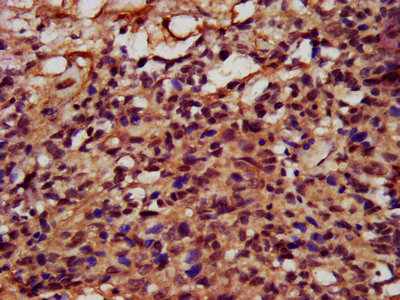

IHC image of CSB-PA839274LA01HU diluted at 1:400 and staining in paraffin-embedded human ovarian cancer performed on a Leica BondTM system. After dewaxing and hydration, antigen retrieval was mediated by high pressure in a citrate buffer (pH 6.0). Section was blocked with 10% normal goat serum 30min at RT. Then primary antibody (1% BSA) was incubated at 4°C overnight. The primary is detected by a biotinylated secondary antibody and visualized using an HRP conjugated SP system.